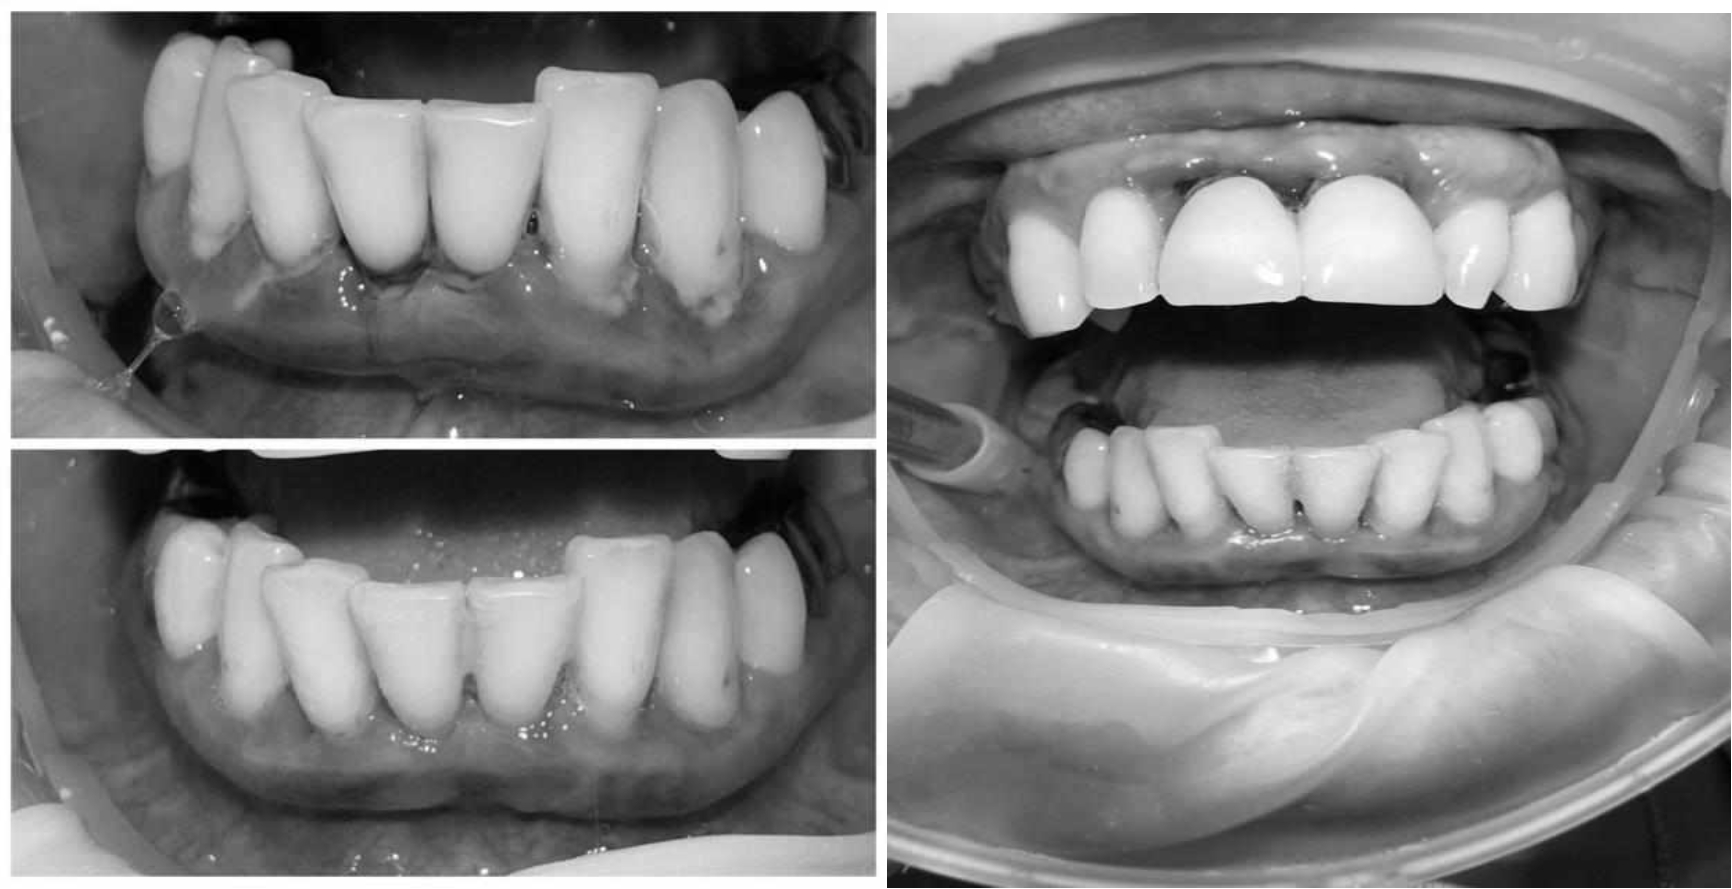

За пародонтологическим лечением обратилась женщина 61 года с жалобами на неприятный запах из полости рта, кровоточивость десен при чистке зубов, подвижность зубов, несостоятельность ортопедических конструкций.

Ранее у пародонтолога не наблюдалась. При осмотре выявлены: неудовлетворительная индивидуальная гигиена полости рта, пародонтальные карманы до 7 мм, обильная кровоточивость и гноетечение из пародонтальных карманов, подвижность зубов 4.2, 4.1, 3.1, 3.2 II степени, обильные над- и поддесневые зубные отложения (рис. 1). На ортопантомограме отмечается резорбция костной ткани до ½ длины корня, очаги остеопороза (рис. 2). Пациенту был поставлен диагноз хронический генерализованный пародонтит тяжелой степени тяжести. При осмотре была составлена пародонтограмма с использованием компьютерного зондирования (рис. 3).

Рис. 1. Внешний вид

Рис. 2. Ортопантомограмма исходной ситуации пациента состояния полости рта

Через 6 месяцев при осмотре выявлен удовлетворительный уровень индивидуальной гигиены, отсутствие участков кровоточивости и гноетечения (рис. 4), пародонтальные карманы уменьшились в размерах (рис. 5). Пациент отмечает значительные улучшения. После стабилизации пародонтологического статуса пациент направлен для дальнейшего ортопедического лечения.

Рис. 4. Динамика результата через 6 месяцев